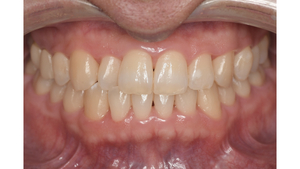

症例2

Before

症例

after

歯周病検査(治療前)

歯周病検査(治療後)

レントゲン写真

基本情報

年齢・性別 41歳・男性

主訴 主訴:歯ぐきから出血する

治療部位:全顎

治療内容 1.歯周ポケット検査、資料取り(レントゲン写真14枚・口腔内写真)、歯磨き指導

2.歯磨き指導チェック、縁上の歯石除去

3.縁下の歯石除去4回

4.再評価(歯周ポケット検査・レントゲン写真14枚・口腔内写真)

5.メインテナンス

治療期間 1日

治療費 合計:14,160円

内訳(全て保険診療3割負担)

・初診検査、歯磨き指導、縁上の歯石除去:3,630円

・レントゲン写真、縁下の歯石除去①:3,040円

・縁下の歯石除去②:1,530円

・歯磨き指導チェック、縁下の歯石除去③:2,070円

・縁下の歯石除去④:1,530円

・再評価:2,360円

(2022年5月現在現在)

リスク・副作用 ・歯石除去後すぐは歯ぐきを触っているため歯ぐきに違和感や痛みを感じる場合がある

・歯石除去により今まで腫れていた歯ぐきが引き締まり歯ぐきが下がる可能性がある

・歯ぐきが引き締まって下がることにより歯面が今までより露出し知覚過敏の症状がでる可能性がある

・歯石除去後、歯磨きを怠ると細菌が歯周ポケットのより深部まで入ってしまうため歯周病が悪化してしまう可能性がある

・一度歯周病になると再発しやすい為、定期的なメインテナンスが必要になります

治療方針 1.歯磨き指導

2.歯ぐき上の歯石除去

3.歯ぐき下の歯石除去

4.再評価

5.定期的なメインテナンス

特記事項 ・着色除去(PMTC)は自費治療のため希望しませんでした。

・右下7番の歯周ポケット5mmは親知らずの関係もあり、このまま維持していくことを説明しています。

・他4mmの歯周ポケットに関しては歯垢が少し残っていた為、再度歯磨き指導と、縁下の歯石を確認して様子をみることにしました。

担当者所見 全体的に出血が見られたのと、奥の歯ぐきは炎症があり歯周ポケットが深かった為、まずは歯ブラシの当て方+歯間ブラシ3Sサイズを使用して頂き炎症を落ち着かせました。

両方毎日使用して頂いた為、スムーズに歯周病治療を行うことができました。毎日のホームケアが不十分だと、なかなか結果に繋がらず、治療期間も長くかかってしまう為、患者様の協力が歯周病治療を成功させるためにはかなり重要になっていきます。

そして一度病気になった歯ぐきは再発しやすい為、今後は3ヶ月に1度の定期的なメインテナンスで、この状態を維持できるよう一緒に管理していきます。